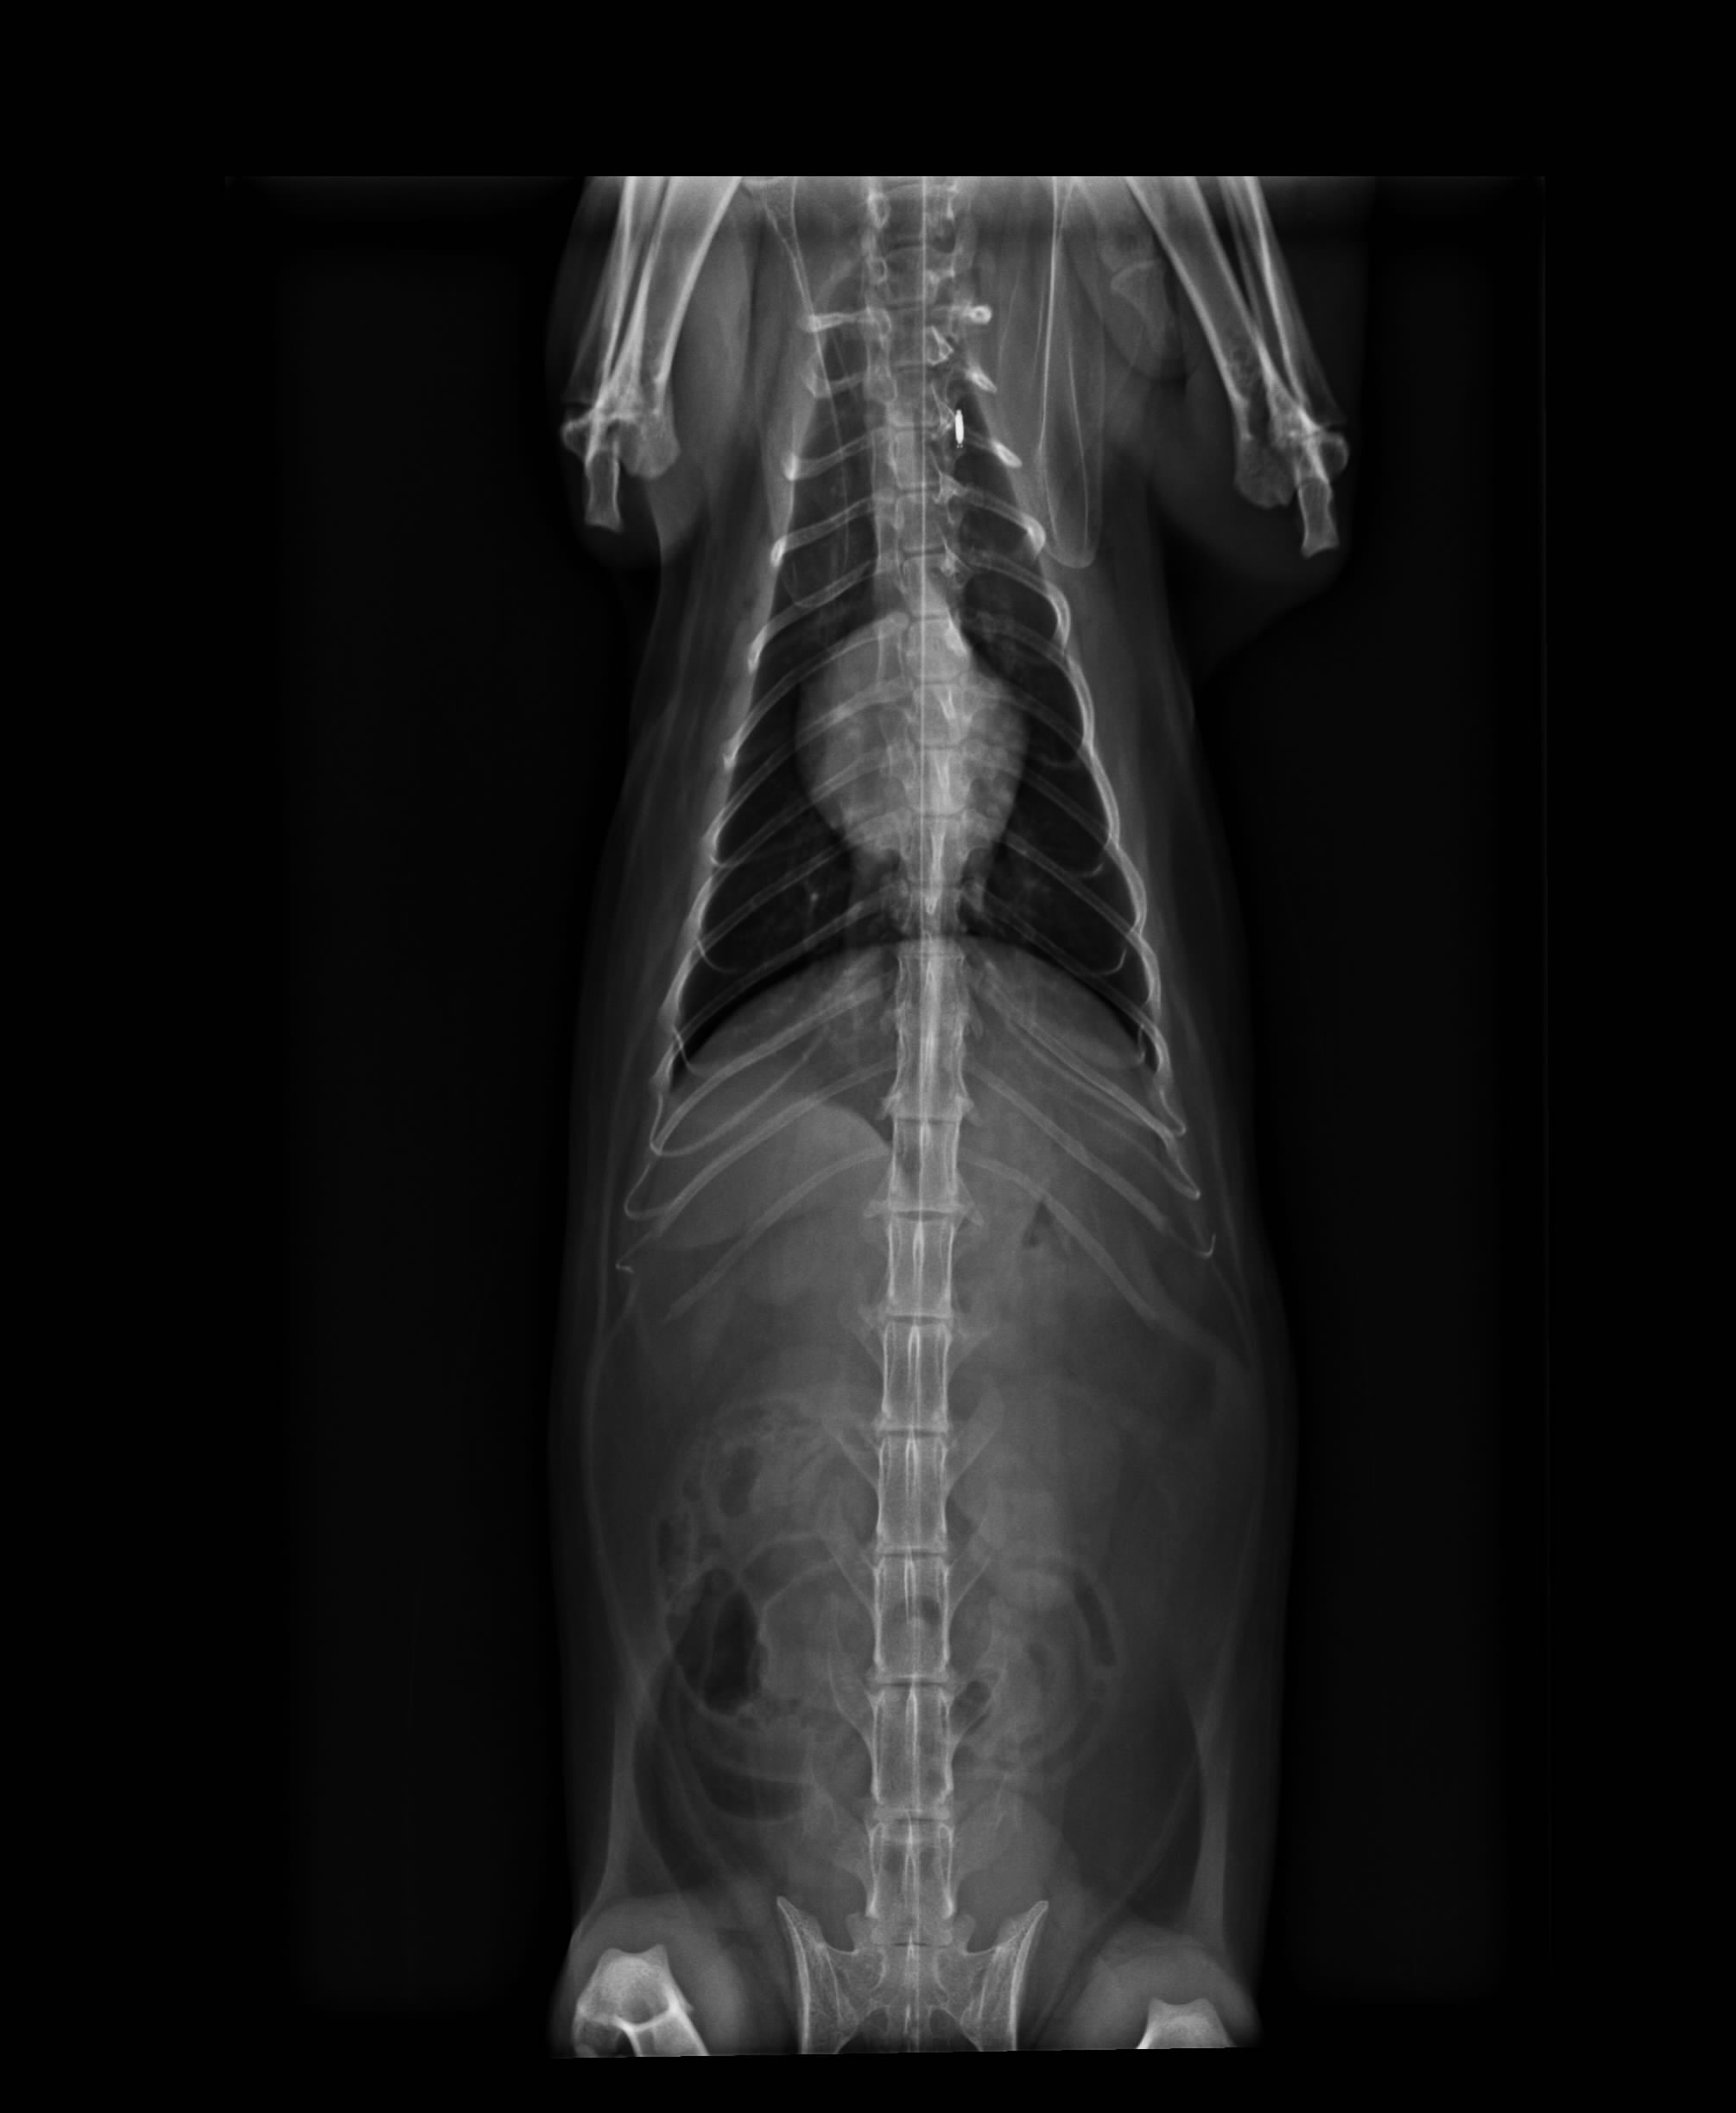

5.X-ray 400*2